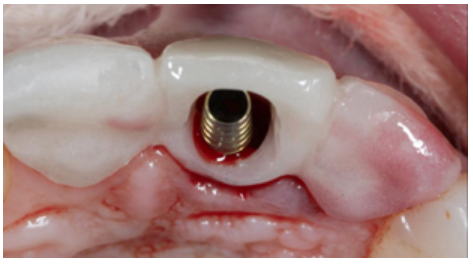

The OII (Neo AlphaBio Medical10™ 3.25mm x 11mm) was inserted at a depth with respect to the future gingival margin that needed to be achieved, 4 mm away from the shoulder of the OII. In this case, the reference gingival margin was that of the ULCI itself, since it was intact and unchanged; while, in the case of the URCI, there was a gingival recession of 2 mm. In this process, the choice of OII diameter was taken so that a space or “gap” would be obtained to facilitate reconstruction of the vestibular cortical bone, paying special attention to the gingival phenotype, to allow for management of the soft tissues also (Figures 7A and 7B).

Primary stability was obtained, achieving anchorage in the palatal residual bone at an insertion torque of 35 N/ cm2 . Subsequently, a temporary prosthetic abutment was placed.